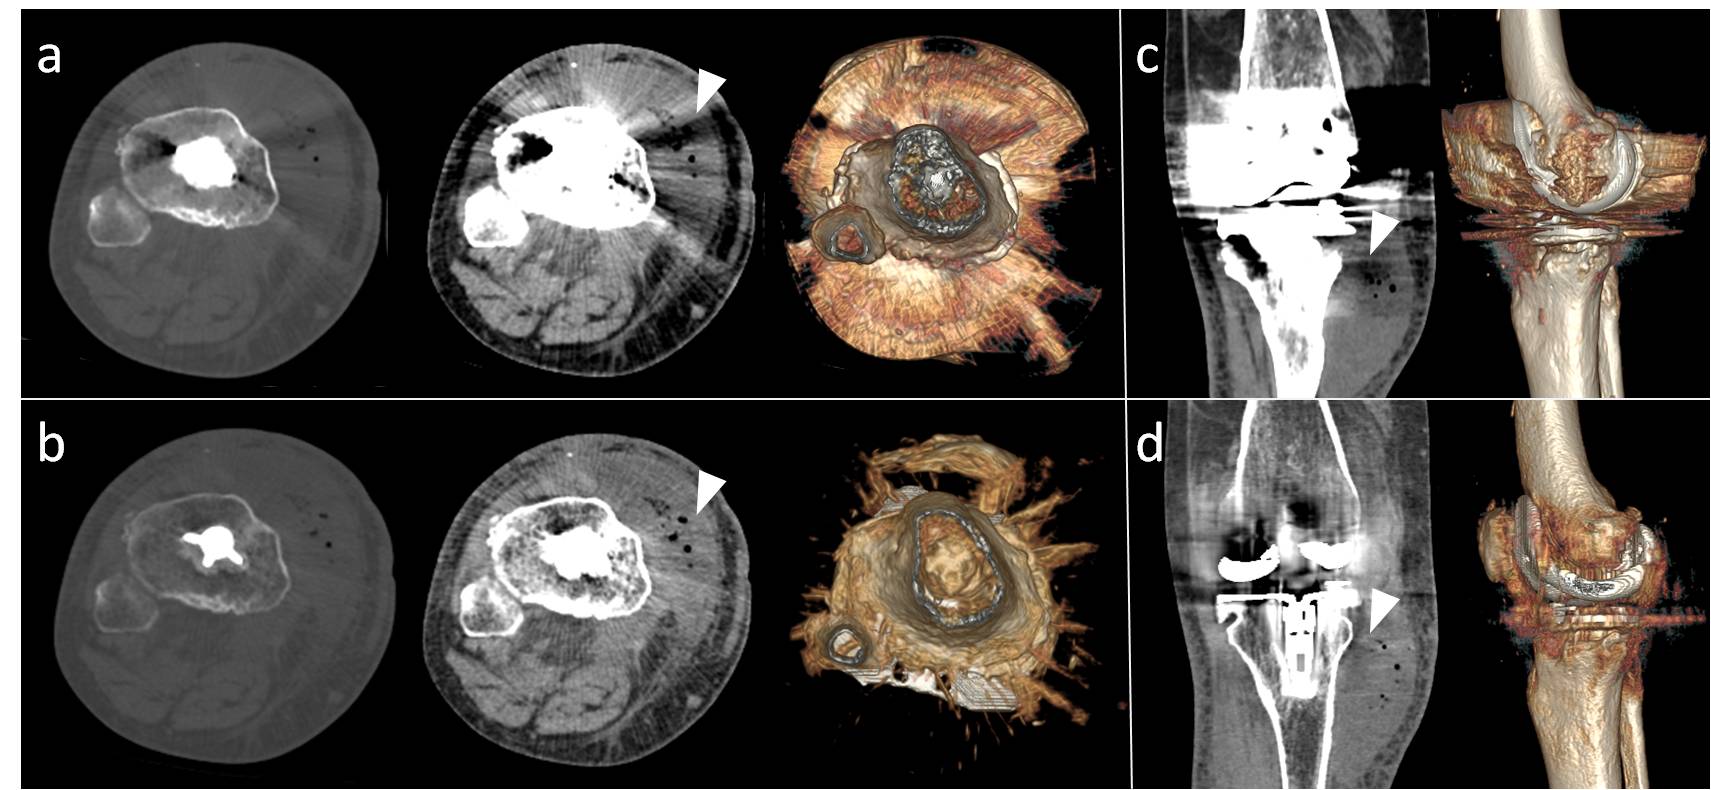

14. Lee YH, Park KK, Song HT, Kim S, Suh JS. Metal artefact reduction in gemstone spectral imaging dual-energy ct with and without metal artefact reduction software. European radiology. 2012;22:1331-1340

15. Lewis M, Reid K, Toms AP. Reducing the effects of metal artefact using high kev monoenergetic reconstruction of dual energy ct (dect) in hip replacements. Skeletal radiology. 2013;42:275-282

17. Guggenberger R, Winklhofer S, Osterhoff G, Wanner GA, Fortunati M, Andreisek G, Alkadhi H, Stolzmann P. Metallic artefact reduction with monoenergetic dual-energy ct: Systematic ex vivo evaluation of posterior spinal fusion implants from various vendors and different spine levels. European radiology. 2012;22:2357-2364